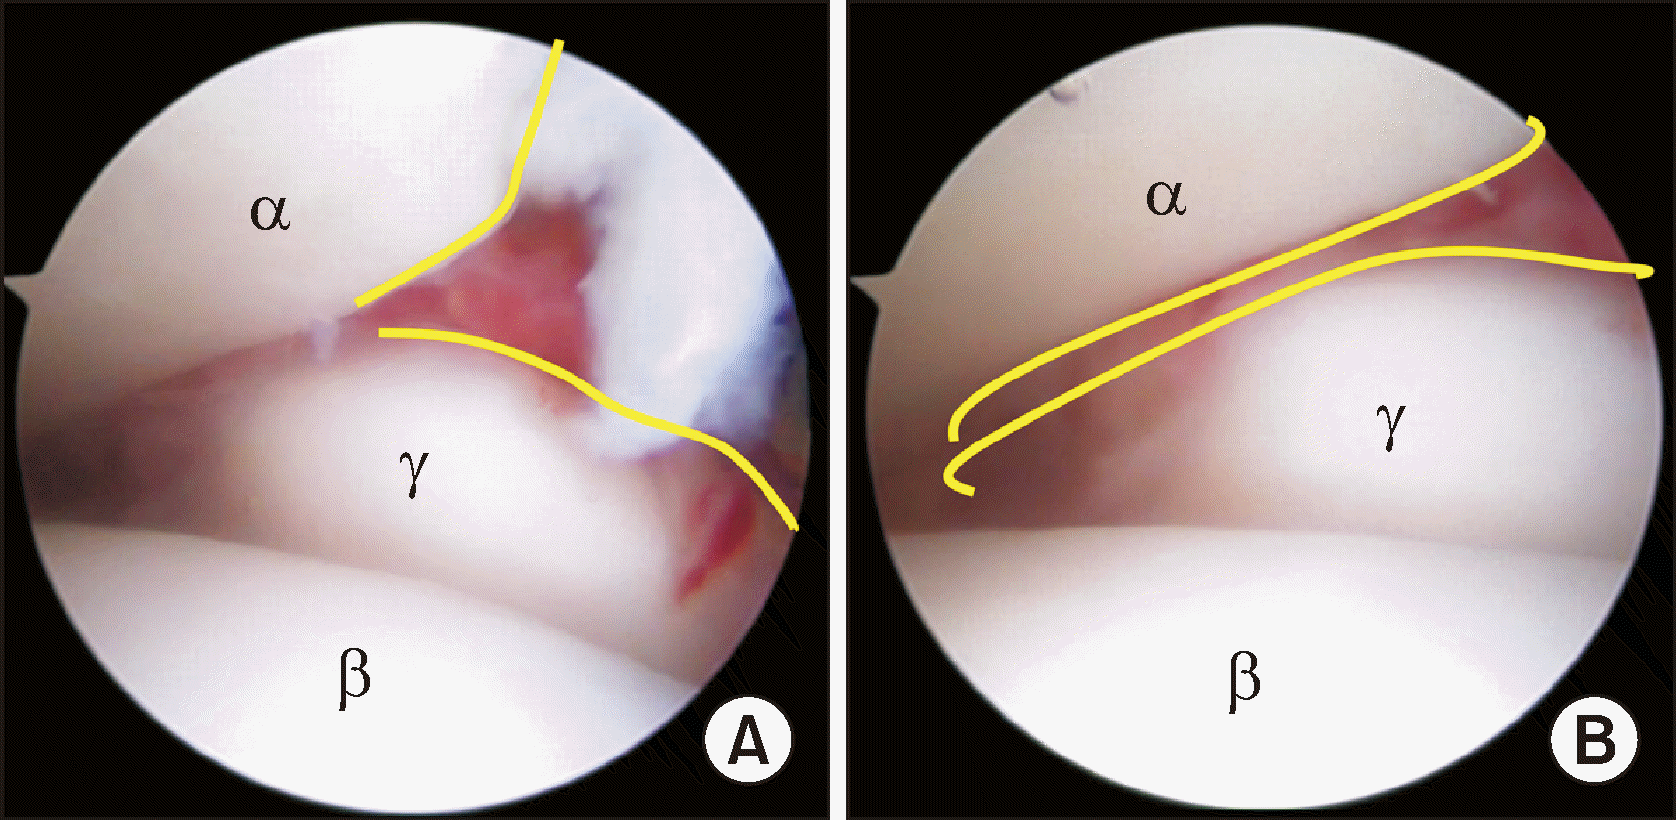

Figure 2

(A) Arthroscopic findings in ankle fracture through the anteromedial portal show an osteochondral lesion of talus. (B, C) Arthroscopic microfracture was performed after debridement. αTibia, βTalus, γOsteochondral lesion.

Figure 3

A widening of 2 mm or more, into which an arthroscopic probe can be inserted during arthroscopic examination, indicates a syndesmosis injury. αTibia, βTalus, γFibula, δArthroscopic probe.